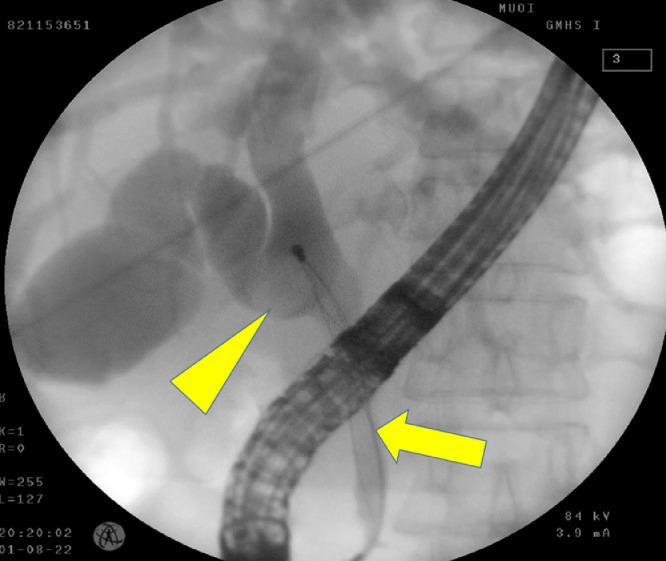

Mirizzi syndrome is a rare chronic cholecystitis complication. However, the current consensus on managing this condition remains controversial, especially through laparoscopic surgery. This report describes the feasibility of treating type I Mirizzi syndrome with laparoscopic subtotal cholecystectomy and electrohydraulic lithotripsic gallstone removal. A 53-year-old woman presented with dark urine and right upper quadrant pain for 1 month. On examination, she was jaundiced. Blood tests showed highly elevated liver and biliary enzyme levels. Abdominal ultrasound showed a slightly dilated common bile duct with suspicion of choledocholithiasis. However, endoscopic retrograde cholangiopancreatography showed a narrowed common bile duct extrinsically compressed by a gallstone in the cystic duct, establishing a Mirizzi syndrome diagnosis. Elective laparoscopic cholecystectomy was planned. At operation, the trans-infundibulum approach was used since dissection around the cystic duct was difficult due to severe local inflammation of Calot's triangle. The gallbladder's neck was opened, and the stone was removed by lithotripsy via a flexible choledochoscope. Common bile duct exploration through the cystic duct was normal. The fundus and body of the gallbladder were resected, followed by T-tube drainage and suturing of the gallbladder's neck. The patient's postoperative clinical course was uneventful. Treating Mirizzi syndrome remains a major challenge for hepatobiliary specialists even with open surgery due to high complication rates, including bile duct injuries. Treatment is primarily to clear out the responsible stone and necrotic tissue. Due to advances in endoscopic surgery and equipment, subtotal cholecystectomy with laparoscopic gallstone extraction provides a safe and effective option for patients with Mirizzi syndrome. Laparoscopic subtotal cholecystectomy with electrohydraulic lithotripsy is a feasible and useful approach for treating Mirizzi syndrome that avoids iatrogenic bile duct injury.

Mirizzi综合征是一种罕见的慢性胆囊炎并发症。然而,目前对于该病症的治疗共识仍存在争议,尤其是通过腹腔镜手术治疗时。本报告描述了采用腹腔镜次全胆囊切除术及电液压碎石取石术治疗Ⅰ型Mirizzi综合征的可行性。一名53岁女性因尿色深及右上腹疼痛1个月前来就诊。检查发现她有黄疸。血液检查显示肝酶和胆酶水平显著升高。腹部超声显示胆总管轻度扩张,怀疑有胆总管结石。然而,内镜逆行胰胆管造影显示胆总管因胆囊管内结石而受到外在压迫变窄,从而确诊为Mirizzi综合征。计划进行择期腹腔镜胆囊切除术。手术中,由于胆囊三角区严重局部炎症,难以在胆囊管周围进行解剖,因此采用经胆囊漏斗部入路。打开胆囊颈部,通过可弯曲的胆总管镜用碎石术取出结石。经胆囊管探查胆总管正常。切除胆囊底部和体部,随后放置T管引流并缝合胆囊颈部。患者术后临床过程顺利。即使是开放手术,治疗Mirizzi综合征对于肝胆专科医生来说仍是一项重大挑战,因为其并发症发生率高,包括胆管损伤。治疗主要是清除责任结石和坏死组织。由于内镜手术和设备的进步,腹腔镜胆囊取石次全胆囊切除术为Mirizzi综合征患者提供了一种安全有效的选择。腹腔镜次全胆囊切除术联合电液压碎石术是一种治疗Mirizzi综合征的可行且有用的方法,可避免医源性胆管损伤。